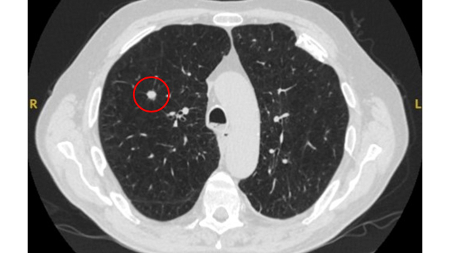

Tomografia computadorizada (TC) mostrando granuloma calcificado benigno no lobo médio direito, estável há >10 anos. O paciente relatou pneumonia prévia no mesmo lado

Do acervo de Dr. George Tsaknis, MD, PhD, FRCP (Londres), MRQA, MAcadMEd, PGCert; usado com permissão